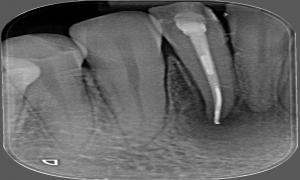

Zub s veľkým zápalom okolo hrotu koreňa

Zaplnenie koreňového kanálika s viditeľne zmenšeným zápalom